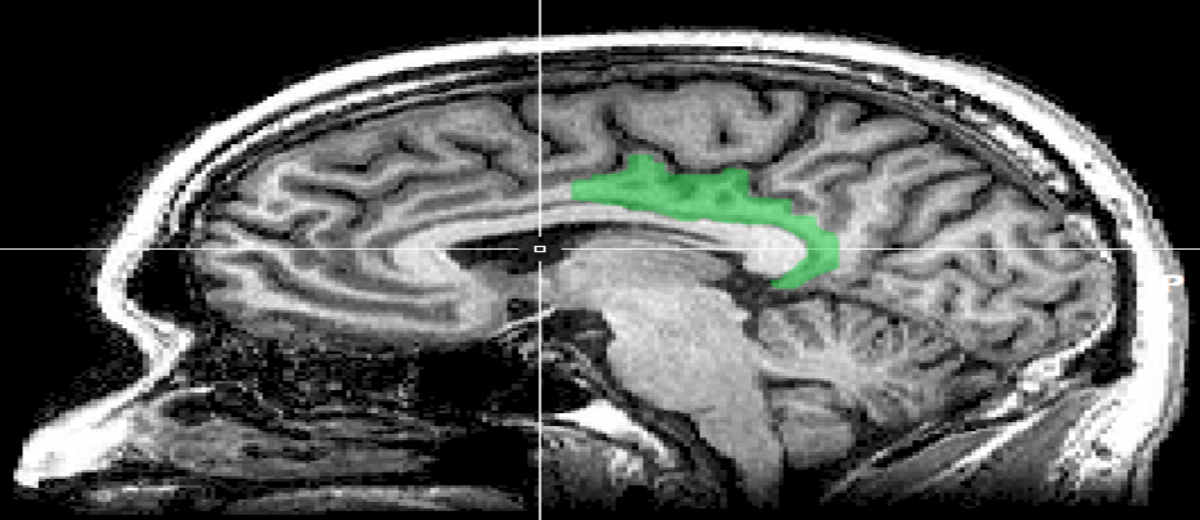

Brain Area Attacked by Alzheimer’s Links Learning and Rewards

Researchers question whether the posterior cingulate cortex actively dampens cognitive performance or monitors performance and attempts to improve it when required.